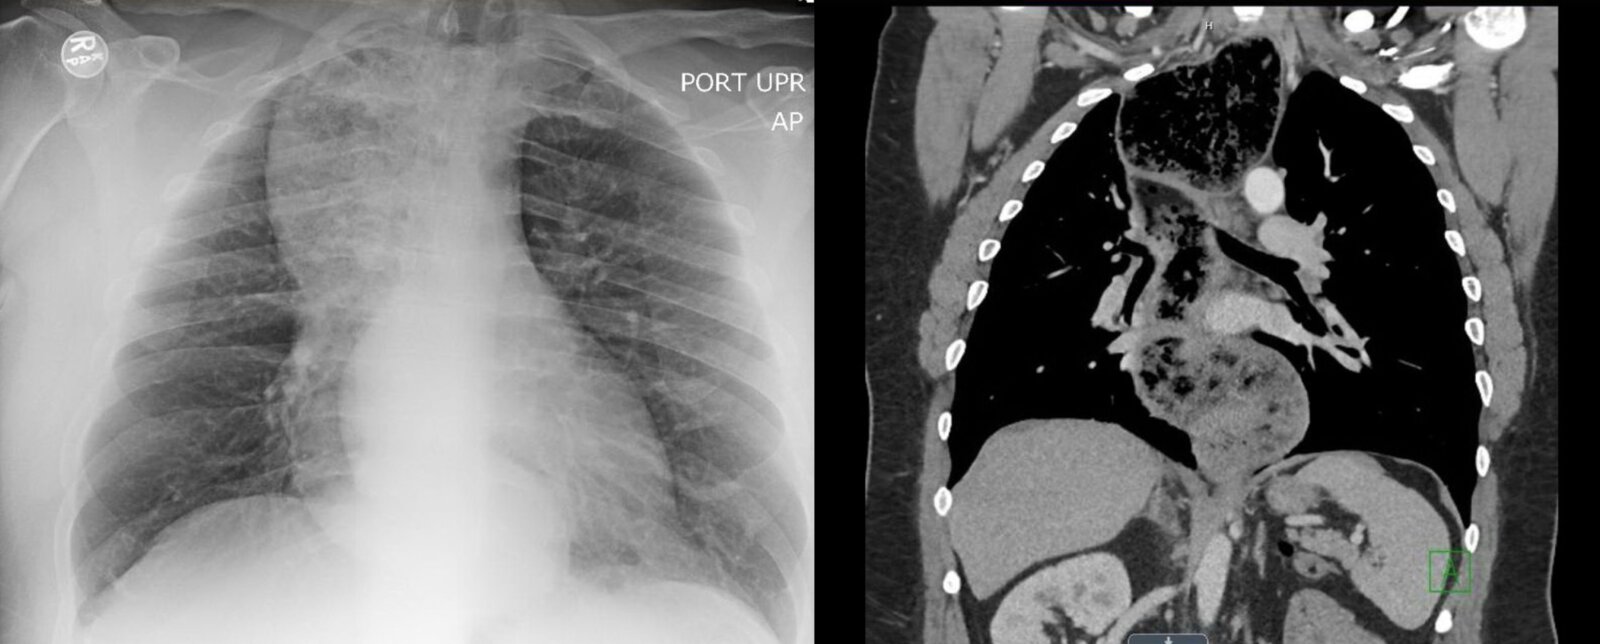

• Chest x-ray

• Not routinely indicated

• May show supportive findings, e.g.: [6]

• Widened mediastinum

• Air-fluid level on lateral view

• Possible absence of gastric bubble

• Cross-sectional imaging: for further evaluation if malignant causes of pseudoachalasia are suspected [2]